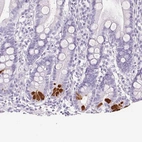

Immunohistochemistry analysis in human pancreas and cerebral cortex tissues using HPA063471 antibody. Corresponding PRSS1 RNA-seq data are presented for the same tissues.